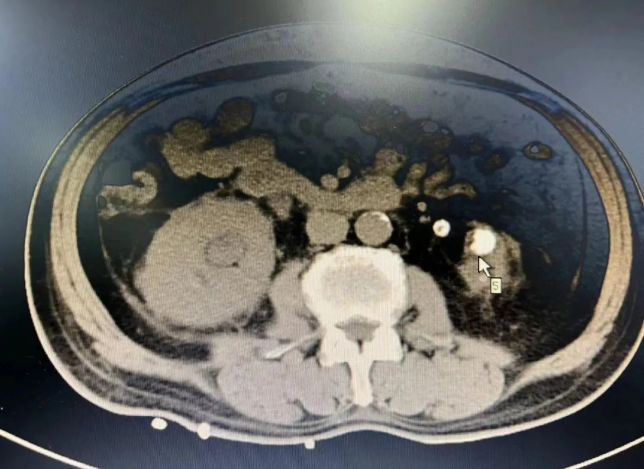

泌尿外科副主任医师王国昆介绍道:“经检查患者病情后,首先考虑患者高龄并卧床休养很长时间,心肺功能差,左肾萎缩已无功能,长期透析治疗已经引发贫血、电解质紊乱等多种疾病,此外,右侧输尿管结石梗阻引起肾功能衰竭。”

经科室医护团队研判需及时开展手术,解除右侧输尿管结石梗阻,保护好仅有的右肾功能。但难题来了,患者只有一个右肾,行经皮肾镜碎石取石手术风险较大,万一术中或术后大出血无法止血,手术团队将面临切除右肾的风险,后果不堪设想。主管医师马青冬建议手术时需选择最佳穿刺点,轻柔操作避免大出血风险,术前做好充分备血准备。

团队达成一致意见,术前先经我院肾内科血液透析治疗改善肾功能,再由泌尿外科给予行右侧经皮肾盂钬激光碎石取石治疗,先保住右肾,再进行下步治疗。